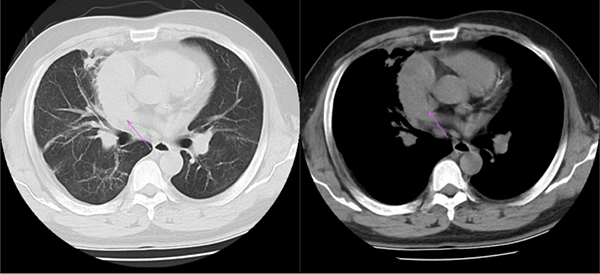

图:侯阿姨的CT片,肿物主要位于右侧纵隔,波及左侧,压迫右肺上叶(右图长箭头),但与上腔静脉(短箭头)和主动脉(长箭头)界限清晰

对于侯阿姨的病情,刘志东主任根据CT检查做出了精确的判断:“虽然这个患者肿物比之前老康的更大,但与周围组织尤其是主动脉、上腔静脉、心包等界限清楚,并未发生侵袭,右肺上叶主要为压迫性肺不张,整体手术难度低于老康。”在刘志东主任的带领下,纵隔外科团队又向纵隔肿物发起了挑战。经术中探查,病变位于前上纵隔,大小约12cm×14cm×10cm,质地较硬,侵及右肺上叶,且右肺上叶部分肺出现肺不张、肺实变。在此情况下,刘志东主任团队仅用30分钟,就完成了纵隔肿瘤的切除,纵隔外科团队再次创造了奇迹。